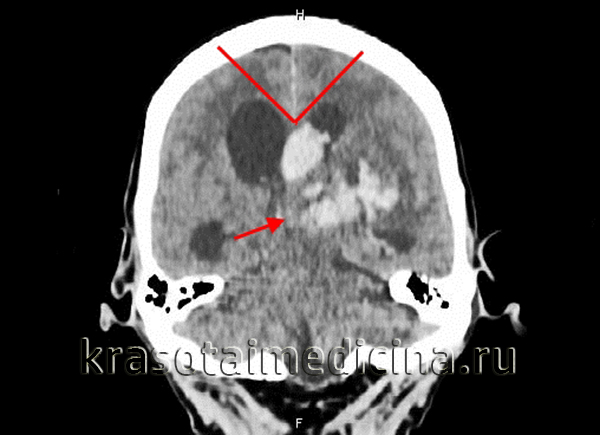

КТ головного мозга. Окклюзионная гидроцефалия, обусловленная массивной внутримозговой гематомой. Стрелка – поджатый 3-й желудочек

(Б): подтверждение геморрагической этиологии. а - Окклюзионная гидроцефалия, вызванная обширной опухолью задней черепной ямки.

Длительное развитие заболевания привело к истончению турецкого седла и коры.